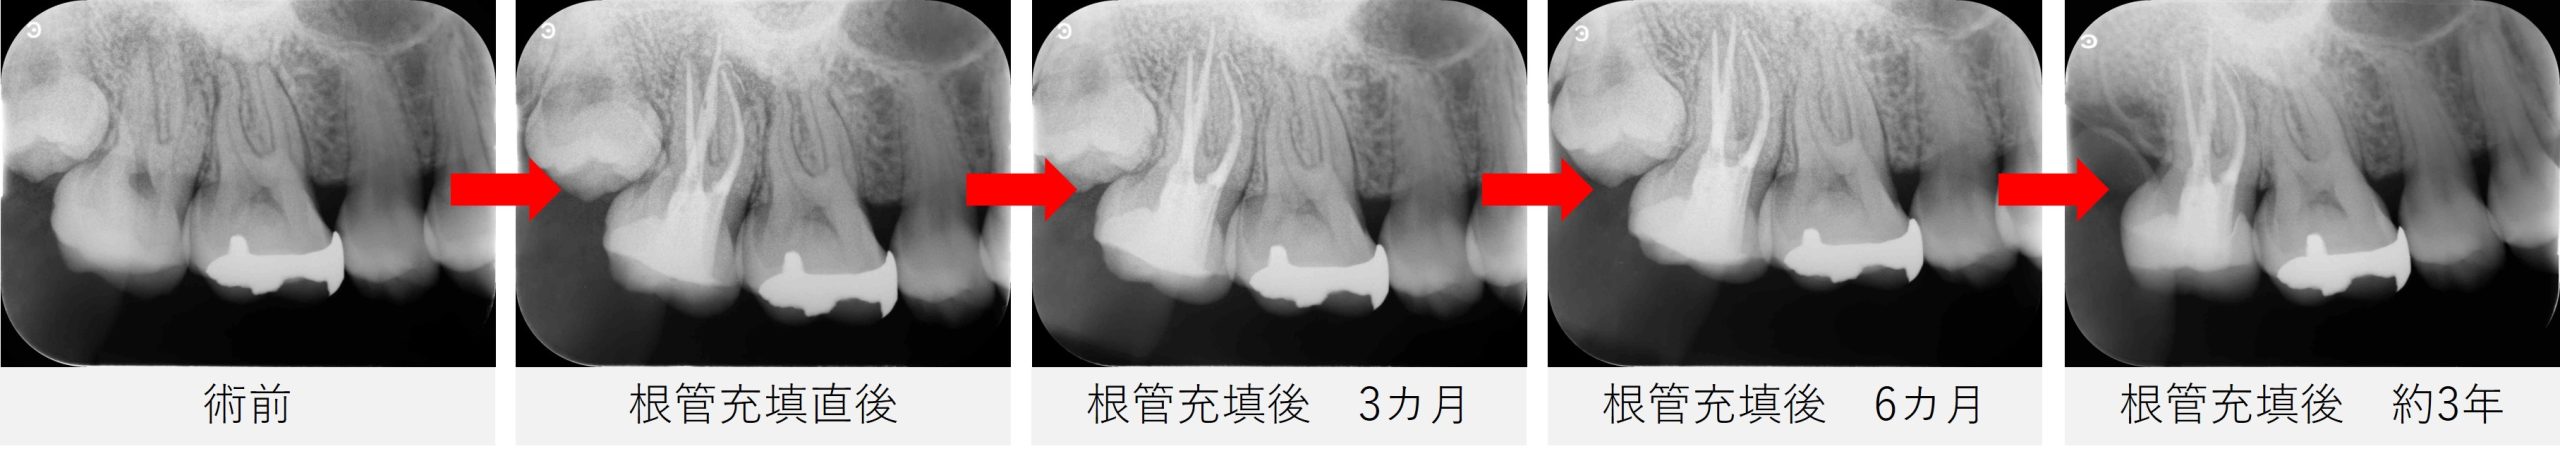

▲根管充填直後のレントゲン画像

根の形が曲がっている部分まで、しっかりと材料が充填されています。

根管充填後は、画像と症状の両面から経過を確認していきました。

根管充填後3か月

- 痛みや腫れなどの症状は落ち着いており、右上6番に見られていた瘻孔(ウミの出口)の再発も認められなかった。

- レントゲンでは、右上7番の根の先に見られていた透過像(黒い影)に大きな変化はなかったが、レントゲンでの変化は時間を要するため、現段階では問題ないといえる。

- 引き続き、経過を観察していく方針とした。

根管充填後6か月

- 自覚症状はなく、噛んだときの痛みや歯ぐきの腫れもみられなかった。

- レントゲン、CT撮影にて、根の先の透過像(黒い影)が小さくなり、改善していることを確認した。

- 回復が進んでいることから、患者さんが希望されていた矯正治療へ進められる状態であると判断した。

根管充填後 約3年

- 「たまに歯ぐきが腫れている気がする」とのことで来院。

- 診査およびレントゲンでは、炎症や再感染を示す所見は認められず、経過は良好と判断した。

- 一度根の先に炎症があった歯は、周囲の組織が回復していく過程で違和感がでることがあるため、今後も必要に応じて経過を確認していく方針とした。